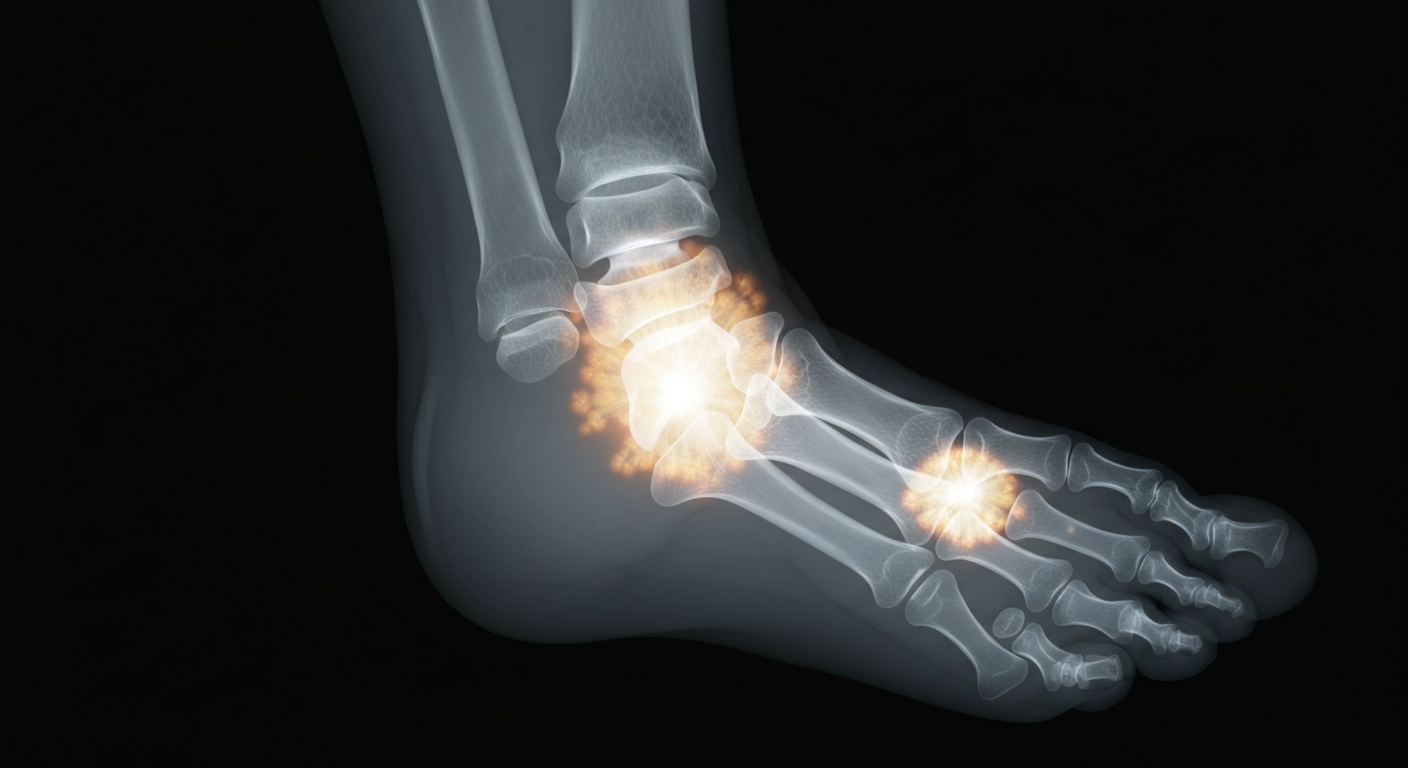

An X-ray view exposes the hidden dangers of an untreated fungal infection that can spread and lead to serious complications.Cleveland TodayAthlete's foot is a common fungal infection that can cause itching, burning, and dry, scaly skin on the feet and toes. While it may seem like a minor issue, it can lead to more serious complications if left untreated, particularly in the elderly, those with diabetes, or people with weakened immune systems. Proper foot hygiene, antifungal treatments, and preventative measures are key to managing athlete's foot and avoiding potential problems like cellulitis.

Athlete's foot, also known as tinea pedis, is a fungal infection that thrives in warm, moist environments like sweaty feet and damp socks and shoes. It can present as dry, scaly skin on the soles or between the toes, blisters, or pustules. The infection can spread easily to others and, if left untreated, can spread to other parts of the body. People with diabetes, peripheral vascular disease, or weakened immune systems face a higher risk of serious complications from athlete's foot, such as cellulitis, a potentially limb-threatening bacterial skin infection.